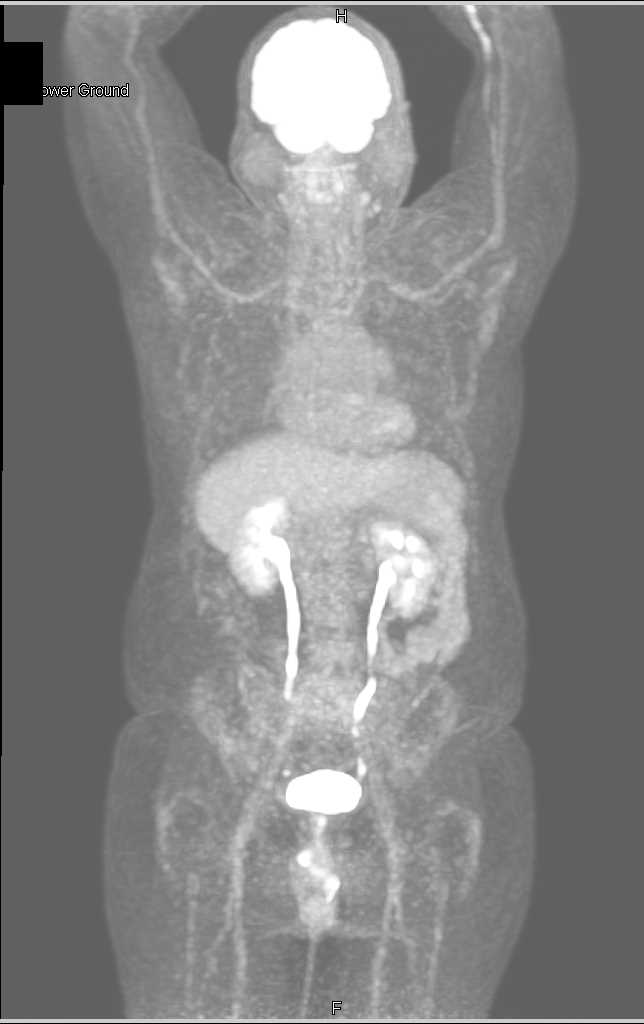

Transitional Cell Carcinoma Right Renal Pelvis